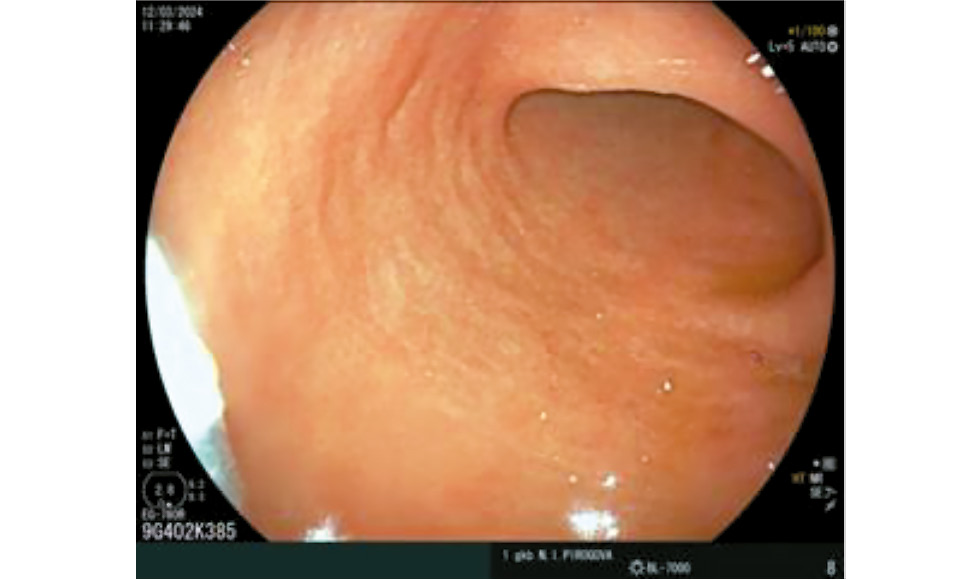

Maruyama et al. identified another endoscopic finding, characterized by visualization of a capillary network without the central opening of fundic glands. This finding was diagnosed in 59% of cases in patients with autoimmune gastritis [48]. The symptom was named the discarded skin sign (Fig. 7) [9].

Fig. 7. Picture of “cast-of skin appearance” — reticular capillary network without gland openings. © Eco-Vector, 2025.